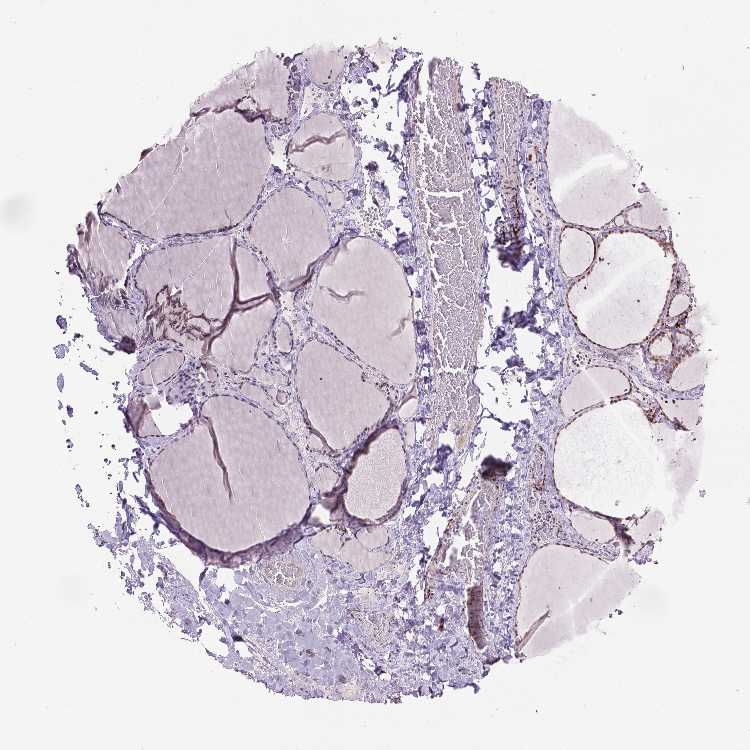

THYROID GLAND - Antibody stainingi

Antibody staining in the annotated cell types in the current human tissue is reported as not detected, low, medium, or high, based on conventional immunohistochemistry profiling in selected tissues. This score is based on the combination of the staining intensity and fraction of stained cells.

Each image is clickable and will lead to virtual microscopy that enables deeper exploration of all samples and also displays staining intensity scores, fraction scores and subcellular localization as well as patient and tissue information for each sample.

Antibody HPA061003Antibody CAB002522Antibody CAB072340

Glandular cells Not detectedNot detectedLow